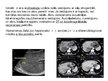

Aknu sarkoma. Klīniskā aina līdzīga citiem aknu ļaundabīgo audzēju simptomiem. Viena no sarkomu īpatnībām ir strauja augšana un visa orgāna infiltrācija, it sevisķ̌i bērniem. Audzējiem ir tieksme sabrukt un radīt asiņošanu vēdera dobumā.

Aknu sekundārie audzēji: var būt kuņģa, resno zarnu, aizkuņģa dziedzera, olnīcu, dzemdes, plaušu u.c. orgnu vēža metastāzes. Sekundāro audzēju biežums svarstās 80 - 90 % robezā̌s no visiem aknu ļaundabīgajiem procesiem. Metastāzes

aknās biezā̌k izraisa vēzis, retāk sarkomas, melanomas u.c. audzēji.

Vairumā gadījumu metastāzes aknās ir multiplas. Klīniski prevalē primāra audzēja simptomātika. Par metastazēšanos aknās liecina hepatomegālija, ascīts, dzeltē.

Transarteriālā ķīmijembolizācija (TACE) Mērķis: Devaskularizācija +tēmēta citostatiskā medikamenta ievadīšana tieši audzēju masā ar augstu koncentrāciju un prolongētu ( ~ 4 nedēļas ) iedarbību Mikrosfēru Ø 45-100 µk Indikācijas: Hepatocelulāra karcinoma - ar doksorubicīnu Kolorektāla vēža metastāzes - ar irinotekānu